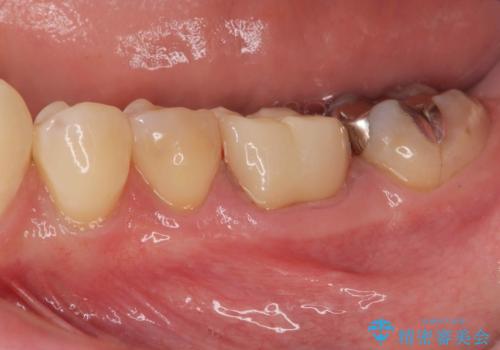

右の奥歯を機能回復|再根管治療とインプラントでしっかり噛める歯へ